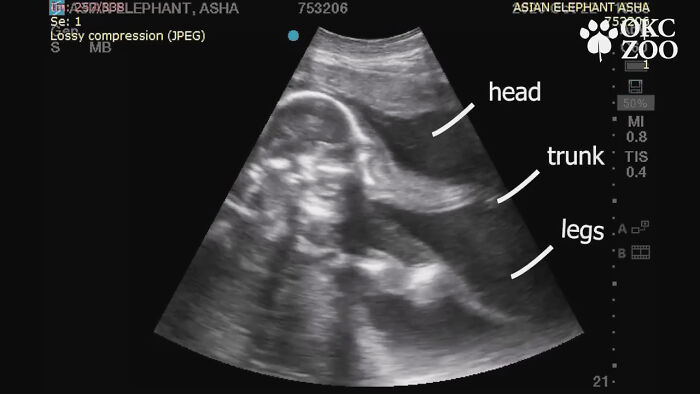

While the world was preoccupied with the coronavirus pandemic back then, a zoo in Oklahoma shared an ultrasound of a baby elephant that made the world stop for a second and all go aww.

Remember the baby elephant ultrasound everyone was talking about back in late November of 2020?

Rama (meaning “pleasing” in Sanskrit) the Asian elephant first came up on the internet radar back in late November of 2020, when Oklahoma City Zoo announced its beloved then 25-year-old mommy elephant Asha, now 26 years of age, was pregnant.

The announcement was made when Asha was 8 months pregnant—that is 8 of the 22 total months (about 660 days) elephant pregnancies last. The original prognosis was sometime in February, 2022, which back then felt like a long way away, but here we are. Rama was born on January 20, 2022, at 8:26 p.m., inside the Zoo’s elephant barn at Sanctuary Asia.